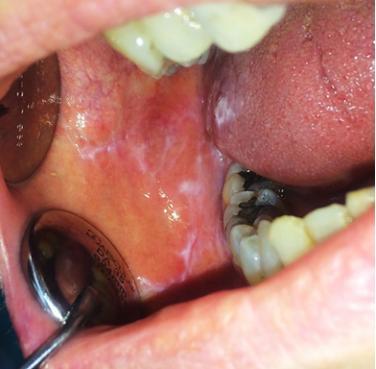

口腔里出现类似“苔藓”的白色斑块,这可能是口腔扁平苔藓的症状。这种疾病虽然听起来陌生,却是口腔黏膜病中仅次于复发性口腔溃疡的常见疾病,在全球的患病率约为0.1%~4%。

口腔扁平苔藓的症状多种多样,可能表现为口腔黏膜上的白色花纹或斑块,患者会感到粗糙不适。这些病变可能出现在舌头、牙龈、嘴唇、腭部等任何口腔内部位置,其中以两侧脸颊的黏膜部位最为常见。除了视觉上的异常,患者还可能在进食辛辣、热、酸、咸味食物时感到局部敏感或灼痛。